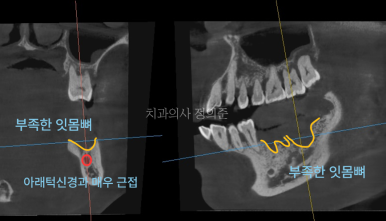

2023. 7

왼쪽 아래 첫번째 큰 어금니의 경우 큰 무리없이 임플란트 수술이 가능하여 1주일 정도 더 기다린 후에

임플란트 수술을 진행하였습니다. (우측 파노라마 사진)

다만, 빠진 2개의 치아 중 제일 뒤쪽 (왼쪽 아래 두번째 큰 어금니)의 잇몸뼈가 많이 부족한 상태셨고,

아래턱 신경과 매우 근접하였기 때문에 안전한 임플란트 식립을 위하여 3개월 정도 회복을 기다린 후에

수술 전에 "서지컬 가이드"라는 장치를 만들고 수술하는 것으로 계획하였습니다.

아래턱 어금니 부위에 임플란트를 식립할 때는, 아래턱을 전반적으로 담당하는 신경인

하치조신경 (Inferior Alveolar nerve)에 손상이 가지 않도록 하는 것이 매우 중요합니다.

빨간색으로 길게 보이는 것이 하치조 신경의 일부 입니다.

서지컬 가이드 없이도 수술이 진행은 가능하지만,

1%의 손상 가능성이라도 있다면,

환자분의 안전을 위해서 모든 불안요소를 줄여야 한다고 생각하기에

이런 경우에는 서지컬 가이드를 활용하여 수술을 진행하고 있습니다.